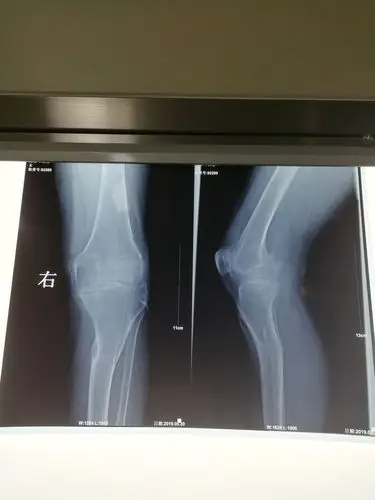

我的膝盖是分层了吗